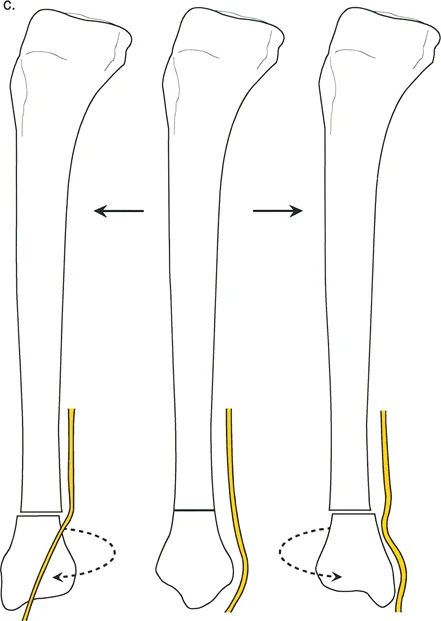

* الدوران الظنبوبي (Tibial Torsion): التواء في عظم قصبة الساق، يمكن أن يكون داخلياً أو خارجياً، ويؤثر على اتجاه القدم.

تحليل دوران قصبة الساق (Tibial Torsion Analysis)

يتبع تحليل دوران قصبة الساق (Tibial Torsion) منطقاً مشابهاً ولكنه يعتمد على معالم تشريحية مختلفة (الكاحلين). يحدد هذا التحليل مدى التواء عظم قصبة الساق.

1. بروتوكول التصوير: يتم الحصول على صورتين بالأشعة السينية (AP و Lateral) للكاحل مع توجيه صابونة الركبة للأمام.

2. القياس: يتم قياس المسافة العرضية بين الكاحل الإنسي والوحشي على كلتا الصورتين.

3. الرسم البياني: يتم رسم هذه القيم على رسم بياني للمستوى المائل لتحديد اتجاه مستوى الكاحلين.

4. المقارنة: تُقارن زاوية الدوران المحسوبة بالجانب الآخر السليم أو بالنطاق الفسيولوجي الطبيعي (عادة 15° ± 5° من الدوران الخارجي).

تحديد مستوى التشوه بدقة

إن تحديد المستوى الدقيق للتشوه الدوراني هو أحد أهم الخطوات في التخطيط الجراحي. على الرغم من أن الدوران هو تشوه زاوي في المستوى المستعرض، إلا أن موقعه على طول العظم (قريب من المفصل أو بعيد عنه) يؤثر بشكل كبير على كيفية تصحيحه وتأثيره على الأنسجة المحيطة.